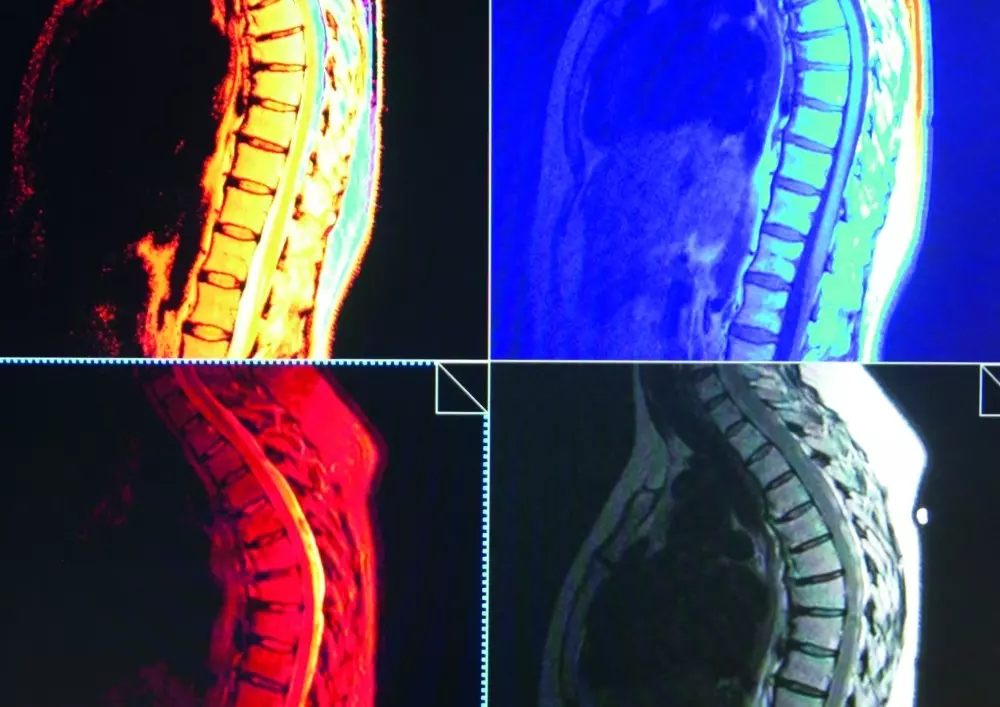

Na łamach naszego czasopisma ponownie pojawia się diagnostyka różnicowa, tym razem w przypadku odcinka piersiowego kręgosłupa i klatki piersiowej. Zachęcamy do zapoznania się z artykułem autorstwa Piotra Godka.